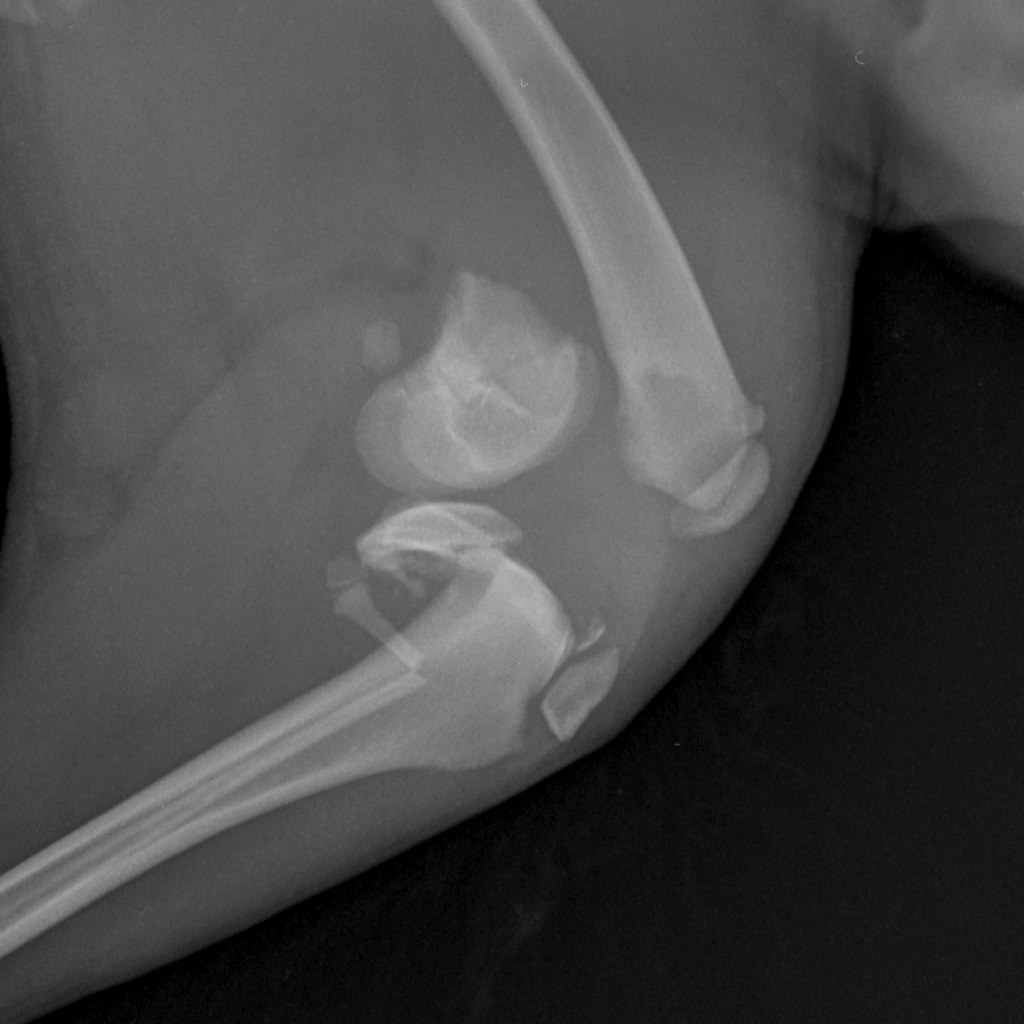

Скелет средний 10-25 kg-Тазовые кости LAT-04.11.2016-14_48_53-472 - копия.jpg

Вот такая бяка у девочки((

Такой мерзкий перелом бывает при прямом ударе по колену

Перелом ужасающий...

Жуть какой перелом! Далекому от медицины человеку - и то смотреть страшно. Впрочем, неудивительно если её из машины на ходу выкинули.